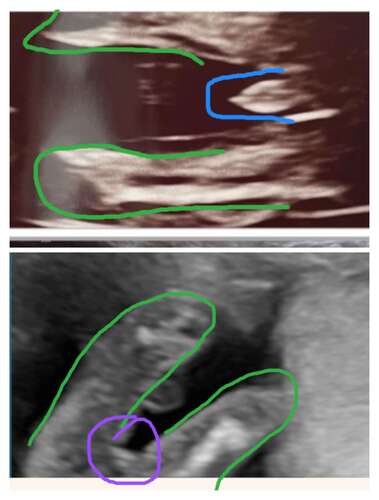

Hier even voorbeeld waar je naar moet kijken. Onderste is jou echo. Bovenst ...

Oh ja nu zie ik het haha 🙈 En het kan ook niet zijn dat de pipi verstopt zit? En ik lees op vorige topics van de pottyshot dat er bij een meisje 3 streepjes of de hamburger teken zichtbaar was, maar die vond ik niet haha 😂 Bedankt voor je voorbeeld alleszins:) 💗💗